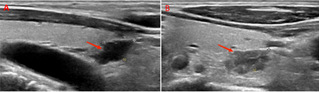

△甲状旁腺B超图:A、B(纵切面)分别提示甲状腺右侧叶下极下方、甲状腺左侧叶下极背侧增生甲状旁腺组织(红色箭头所示)